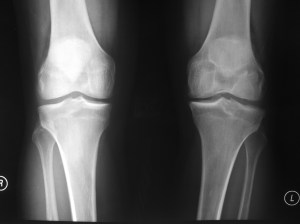

The left knee ACL has been torn for over 10 years while the right knee had an ACL tear just 1 month ago. The above x-rays showed mild narrowing of the left knee medial compartment joint space compared to normal looking joint space in the right knee.

This is an example of knee osteoarthritis from chronic ACL tear.